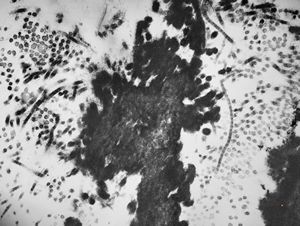

clotted blood - fibrin and granulocytes

F,44y. | striations of fibrin - heart atrium, myxoma

M,28y. | striations of fibrin - aortal valve, endocarditis